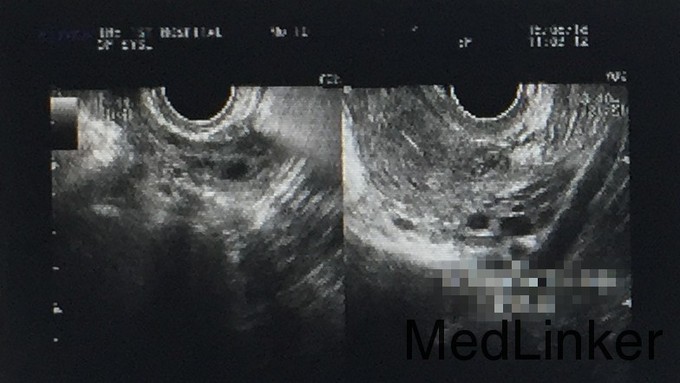

患者女,30岁,主诉:未避孕未孕5年 既往月经规律,5/40天,经量少,无痛经,G5P1A4。 4年前外院行输卵管造影,诊断为双侧输卵管阻塞。

妇检:外阴:发育正常;阴道:通畅,未见异常分泌物,粘膜正常无充血;宫颈:光滑,常大,无接触性出血,无抬举痛,未见活动性出血。宫体:前位,常大,无压痛。双附件:未扪及包块,无触痛。 B超:盆腔未见明显占位性病变。

诊断 1.继发性不孕症;2.双侧输卵管阻塞 处理 宫腹腔镜联合诊治术